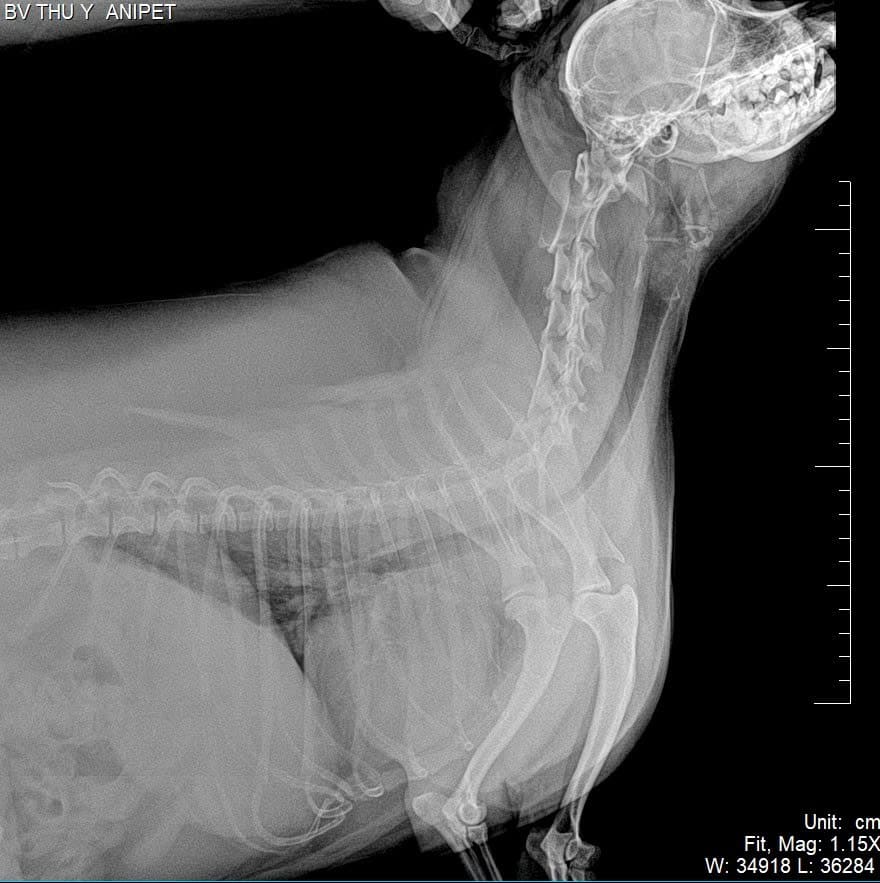

Siêu âm tim và chụp X-quang

Tiếp đến, bác sĩ sẽ tiến hành siêu âm tim và chụp X-quang tim phổi nhằm đánh giá cấu trúc tim, độ dày thành tim và tình trạng phổi. Siêu âm tim giúp quan sát trực tiếp sự co bóp của tim, trong khi X-quang cho biết tim có bị phì đại hay dịch có ứ đọng ở phổi không.

Hai phương pháp này hỗ trợ phát hiện sớm các bệnh lý như suy tim sung huyết hoặc bệnh van tim ở chó mèo.